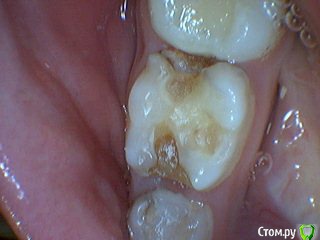

Давлетшин Опубликовано 29 декабря, 2017 Поделиться Опубликовано 29 декабря, 2017 (изменено) Друзья. Расскажите, не поменялось ли ваше отношение к пульпотеку и пр.Почему пломбы поверх пульпотеку такие ужасно жёлтые? Что сделать можно. Или что я делаю не так? "Друзья" так приятно перед новым годом. К пульпотеку не поменялось (устраивает вполне) , к пульподенту скептическое отношение, хоть и тоже работаю. Пломбы сразу желтые или через полгода - год- два? Очень тяжело что то советовать он лайн не видя как человек работает. В фото первая цифра пациент, вторая-третья номер зуба, четвертая порядок фото. Я после наложения пульпотека , стараюсь убрать излишки, или аккуратно на устья каналов накладываю, в пульповую камеру СИЦ, и сверху пломбу, Убрать излишки и со стенок, аккуратно в том числе и бором. В третьем клиническом случае, неудача. Зуб удалил сам же через 3 месяца. причину вижу в том что на рентгене не увидел (или так сделали снимок?) вертикальный тип рассасывания практически до бифуркации., может и потому что ребенок ОЧЕНЬ плохо сидел. За фото не пинайте сильно, не инстаграмм все таки,да и тяжело ребенка лечить и фотки делать. или наоборот пинайте может лучше начнем фоткать. P.s. Добавлю протокол как лечу с пульпотеком, хр.фибр.пульпит1. анестезия2. кофер ( если дает)3. раскрытие кариозной и пульповой камеры4. удаление коронковой пульпы маленьким эскаватором, я стараюсь "отрубать" пульпу5. остановка кровотечения сухим ватным шариком, 0,5-1-2 минуты6. пульпотек на устья7 СИЦ в пульповую камеру8 со стенок остатки пульпотека соскребаю бором фиссурным , цилиндрическим, там же фальц9. Пломба. может что то и зыбыл ну и оценка только позитивная перед НГ Изменено 29 декабря, 2017 пользователем Давлетшин 2 Ссылка на комментарий